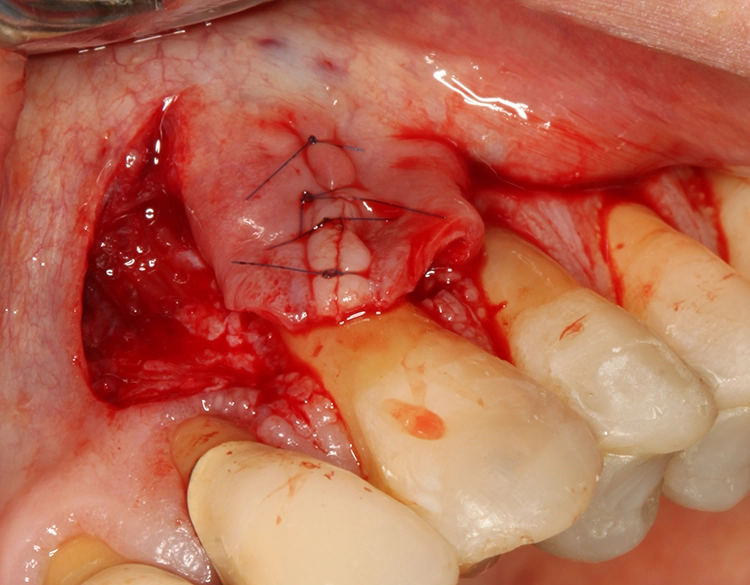

Für die plastische Rezessionsdeckung an den Zähnen 13 und 23 mithilfe von doppelten Papillalappen nach Cohnen und Ross [2], Bindegewebetransplantaten und Schmelz-Matrix-Proteinderivat wurde die Schnittführung mit Split-Flap-Bildung so gewählt, dass möglichst viel keratinisierte Gingiva generiert werden konnte und der Mindestabstand zu den Nachbarparodontien von 1 mm eingehalten wurde (Abb. 13). Ein Gewebekeil wurde apikal der Rezession entfernt und vorerst nur ein Läppchen gesplittet (Abb. 14). Die beiden gesplitteten Läppchen wurden vernäht, wobei ein Mukosaläppchen noch unmobilisiert blieb, um das Aneinandernähen zu erleichtern. Das Vernähen erfolgte von koronal nach apikal, danach wurde das zweite Läppchen vollständig mobilisiert (Abb. 15).

Egger/Wermuth/GrevenAus dem Gaumen wurde mit der Single-Inzisionstechnik [5] ein Bindegewebetransplantat entnommen (Abb. 16). Die Konditionierung der Wurzeloberfläche erfolgte mit EDTA 24%. Schließlich wurde Schmelz-Matrix-Protein (Prefgel/Emdogain, Straumann, Schweiz) appliziert und das Bindegewebetransplantat in der gewünschten Position fixiert. Der Wundverschluss wurde mit nicht resorbierbarem Nahtmaterial (7.0 monofilamentes Polyvinylidenfluorid, Seralene, Serag Wiessner) durchgeführt, die Feinadaptation im Übergangsbereich der beiden lateralen Verschiebelappen mit Einzelknopfnähten. Es wurde kein Wundverschluss per primam angestrebt, um nicht zu viel lateralen Zug auf die Läppchen auszuüben.